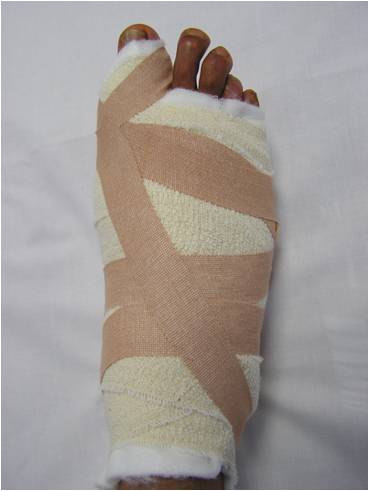

Bunion surgery is carried out as a day case procedure under general, spinal or regional anaesthesia. A regional ankle block (with local anaesthetic) is routinely used for postoperative pain relief (usually lasting 6-8hours). Postoperatively a soft bandage protects the foot (Fig 5) and mobilisation is through a solid-soled postoperative shoe (Fig 6).